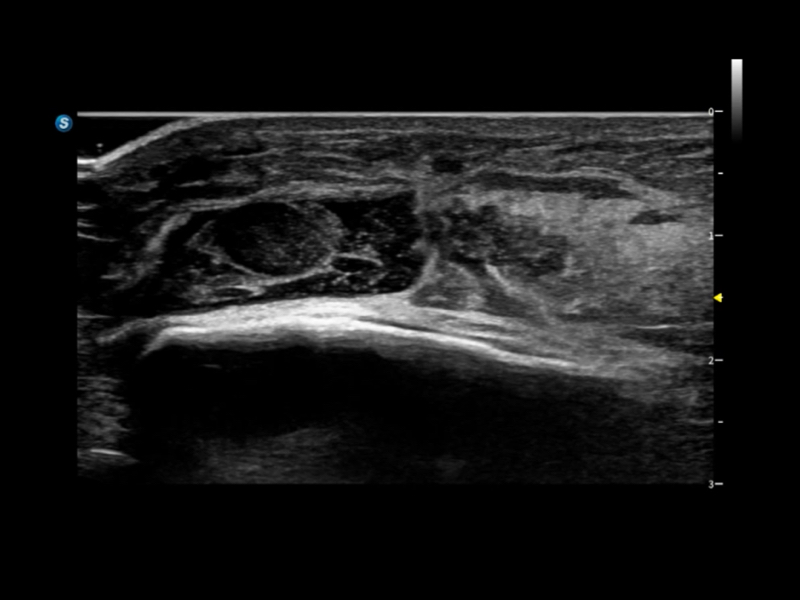

S80 提供多样化超声成像技术,可满足不同科室的需求,在助力扫查诊断和介入治疗中发挥着重要作用。

通过工作流协议、远程访问、自动探头激活和人体工程学优化设计等功能,旨在提高临床工作效率。